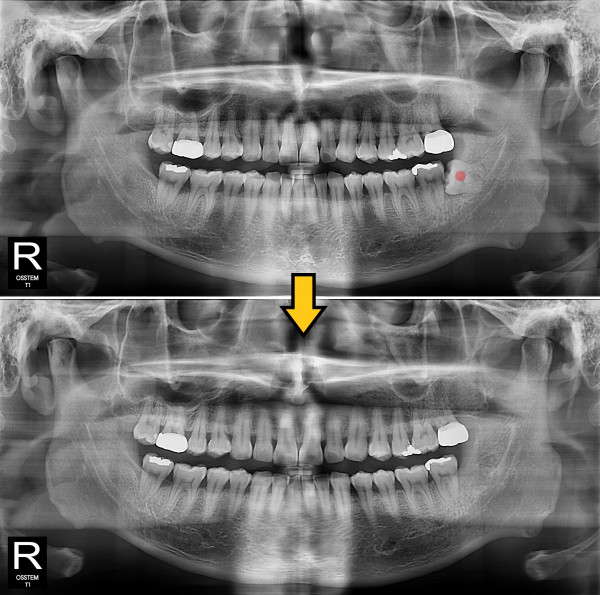

사랑니발치 20대/남성

5e20e086184bc11a2d853605b7813944_1764319730_9574.jpg